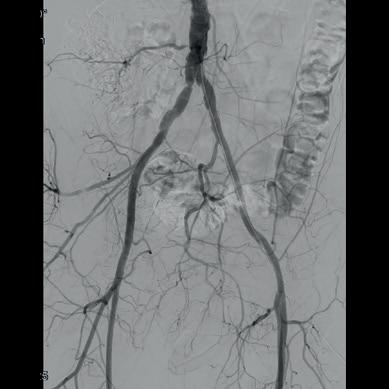

Shockwave intravascular lithotripsy (IVL) “expands endovascular strategies for iliac occlusive disease and can facilitate a ‘leave nothing behind’ approach,” Stefano Fazzini (Tor Vergata University, Rome, Italy) and colleagues write in an open-access Journal of Vascular Surgery (JVS) paper highlighting midterm outcomes from the IVLIAC registry—a multicentre, retrospective study of prospectively collected data.

“CALCIUM REMAINS A CHALLENGE IN the endovascular treatment of iliac artery disease, affecting both procedural and long-term outcomes,” Fazzini tells Vascular News. He goes on to comment that the standard approach of primary stenting, “although effective, is susceptible to stent recoil and under expansion in heavily calcified vessels” and notes that extensive calcification increases the risk of ruptures, especially when high-pressure balloons or balloon-expandable stents are used.

Fazzini also stresses that “no single stent is ideal for all calcified iliac lesions,” and that unnecessary stenting, especially at the bifurcation or when covering key branches, “can be avoided”.

In light of this, Fazzini et al set out to evaluate the midterm outcomes of patients with calcified iliac lesions treated with IVL, with or without adjunctive stenting, and to propose a new algorithm guiding these different treatment strategies.

The new algorithm, Fazzini explains, is based on lesion type (stenosis versus chronic total occlusion) and intraoperative functional assessments (extravascular ultrasound and pressure gradient) to determine whether stenting is necessary. “The impact

of sonic pressure waves improves vessel compliance and luminal gain, but such modifications may not always be evident on digital subtraction angiography alone,” he says, adding that intraoperative functional assessments play a “crucial” role in determining whether IVL alone is enough.

The investigators included all consecutive patients at four centres (Rome, Milan, Negrar and Trento) who underwent treatment with the Shockwave Medical peripheral IVL system for calcified iliac arteries from February 2021 to May 2024. Indication for IVL was Rutherford category of three or above in iliac lesions with moderate-to-severe calcification and was based on the new algorithm. The primary endpoint was primary patency, with assisted primary patency, secondary patency, and freedom from iliac complications also analysed.

Fazzini and colleagues share in JVS that a total of 100 iliac arteries were treated in 86 patients. They note that chronic limb-threatening ischaemia (CLTI) was present in 55% of patients, mean target lesion length was 40.95±29.25mm with a mean stenosis of 84±10%, and 12 of the lesions were chronic total occlusions. The authors report that technical

success was 99% and that target lesions were treated with IVL alone in 77% of cases, whereas IVL plus adjunctive stenting was employed in the remaining 23% of the cases. They add that provisional stenting was performed in 11% of cases, while planned stenting was performed in 12%, and that mean residual stenosis was 14.95±14% at final angiogram. Primary patency and assisted primary patency at 24 months were 95% and 98%, respectively, while secondary patency was 100%. Primary patency showed no statistically significant difference between the IVL only and IVL plus adjunctive stenting groups.

“Shockwave IVL offers a safe and effective treatment option for calcific iliac occlusive disease,” the authors write in their conclusion. “This multicentre experience shows promising midterm results in terms of primary patency despite the very low stenting rate, preserving future treatment options.” They go on to stress that further studies are needed to confirm these findings.

Discussing the findings with Vascular News, Fazzini summarises that, in cases of severely calcified disease, “Shockwave IVL as a first-line strategy in iliac interventions allows for either the avoidance of unnecessary stenting or optimisation of stent expansion, both of which contribute to favourable midterm outcomes”.